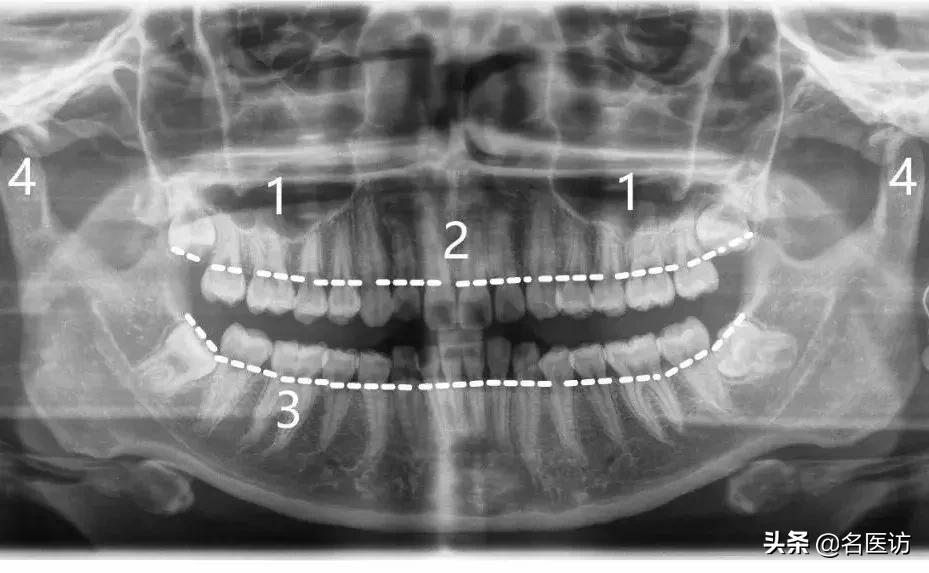

在正式学习之前,我们先来认识几个专业名词:

1:上颌窦

2:牙槽骨

3:牙根

4:髁突